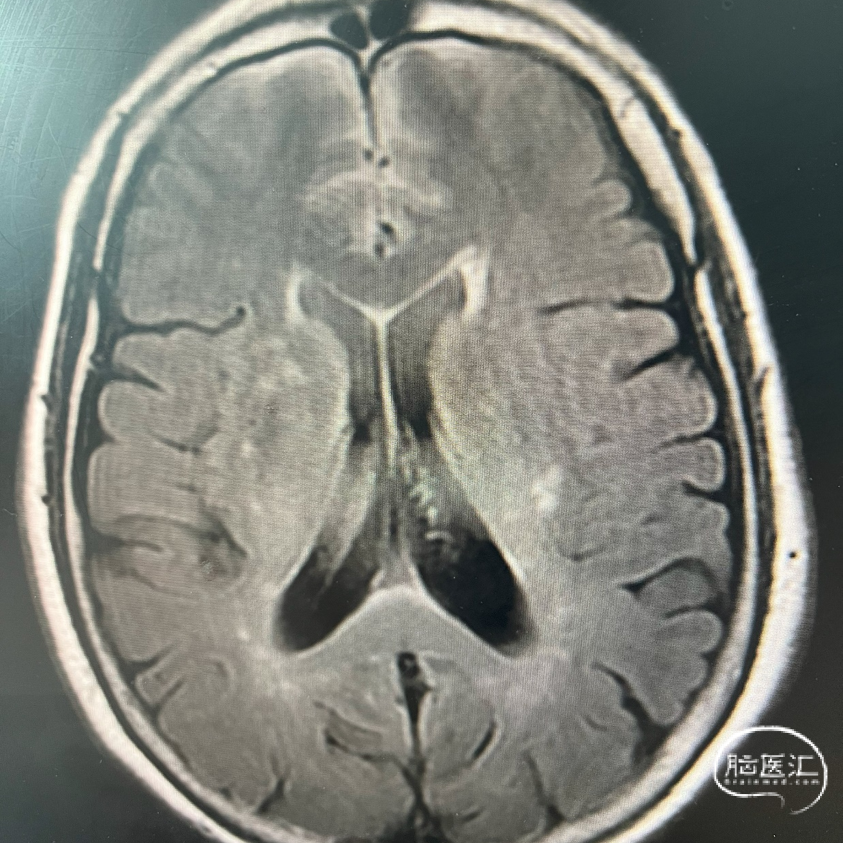

术前FLAIR

术前DWI

影像学表现: